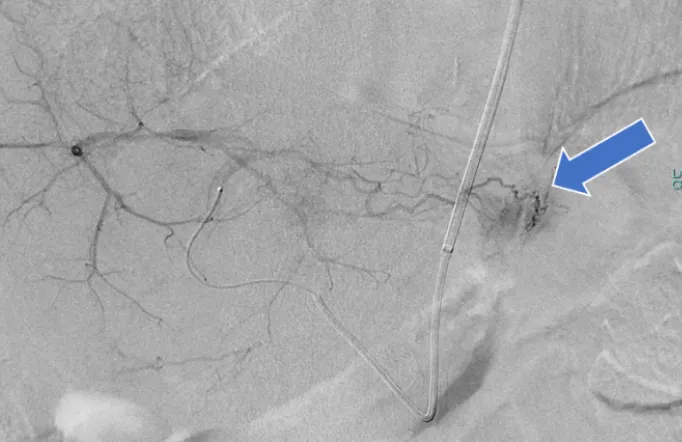

肝がんの検査には、血液検査と超音波(エコー)検査(写真2)、CT検査(写真3)、MRI検査といった画像検査を組み合わせて行います。CT検査やMRI検査では造影剤を使用して詳細な検査を行いますが、腎機能低下や透析症例でも安全に使用できる「造影剤」を用いて行う造影エコー検査(写真4)も週1回外来で行っています。

肝がんの治療法には外科的切除、ラジオ波焼灼療法(写真6)、カテーテル治療(肝動注化学塞栓術)(写真5)、全身薬物療法、放射線治療などがあり、がんの進行度、部位、肝機能などを考慮し、内科、外科、放射線科との緊密な連携のもと、肝がんに対する先進的で集学的な治療を実践しています。当科では、ラジオ波焼灼療法と肝動注化学塞栓術を組み合わせた治療を行っています。また、進行性肝がんの患者さまには免疫チェックポイント阻害薬、分子標的薬を含めた全身薬物療法を行っており、患者さまの病状に応じた治療を行っています。

• (写真5)血管造影検査で肝がんは造影剤で染まる

• (写真7)肝動注化学塞栓術により薬剤が貯留した肝がん